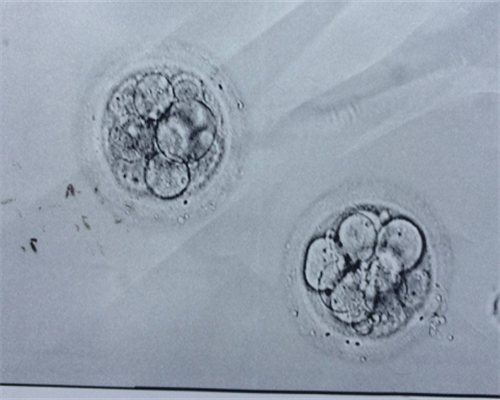

从月经来潮的第一天开始,卵泡就开始生长发育了。卵泡排卵时释放出来的卵子,可以和精子结合形成受精卵,不过卵子并不是时常都在排,一般在排卵期排出卵子,卵子是在月经后几天形成的,而每个女性的排卵情况都不同,这和自身的内分泌激素也有一定关系。

如果女性备孕了半年还没有怀孕的话,跟卵子的质量也有一定关系,女性最好去医院做一下检查,可以通过b超检查一下卵泡的发育情况,查看卵泡发育是否良好。